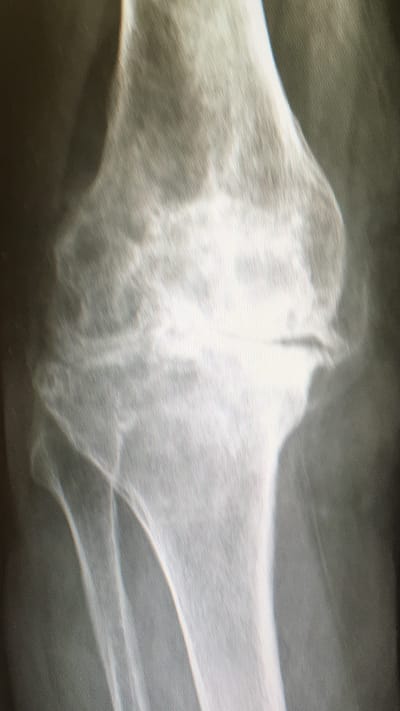

Si stima che in Italia vi siano 4 milioni di persone artrosiche. Sempre l’artrosi è la principale causa di invalidità oltre sessant’anni. L’epidemiologia ci dice che dopo 55 anni più dell’80% dei pazienti manifesta segni radiologici di artrosi: ciò vuol dire che oltre otto persone su 10, se dovessero eseguire una radiografia di un’articolazione, leggeranno nel referto” segni di artrosi”.

Essa rappresenta la degenerazione (usura) dell’articolazione che entro certi limiti va considerata fisiologica. Quando questa usura offre limitazioni funzionali, cioè impedisce lo svolgimento delle normali attività, entriamo nell’ambito patologico e quindi dobbiamo pensare ad un trattamento congruo al fine di restituire una buona qualità di vita.

Quali esami?Nella quasi totalità dei casi le radiografie sotto carico (cioè eseguite mentre il paziente è in piedi ) sono le uniche indagini necessarie.

Esse dimostrano il grado e la localizzazione dell’usura e lo stato legamentoso, consentendo quindi la scelta dell’impianto idoneo.

Nelle radiografie qui sotto si nota come in quella di dx vi è lo spostamento dello stelo femorale rispetto quella di sx: ciò sta ad indicare la mobilizzazione dell’impianto a livello della componete femorale.